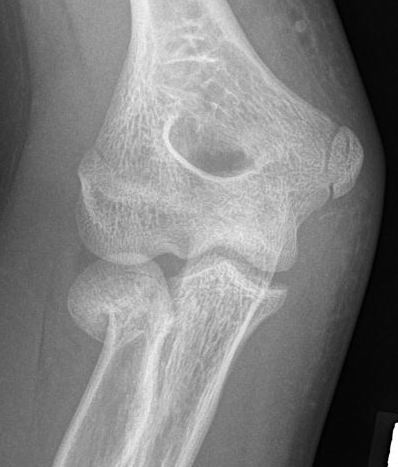

Radial neck fracture and olecranon fracture

Radial neck + olecranon fracture

Chen et al Acta Orthop Traumatol Turc 2023

- 31 cases displaced radial neck + olecranon

- treated with open Boyd approach / flexible nail radial neck / K wire olecranon

- 4/31 poor results